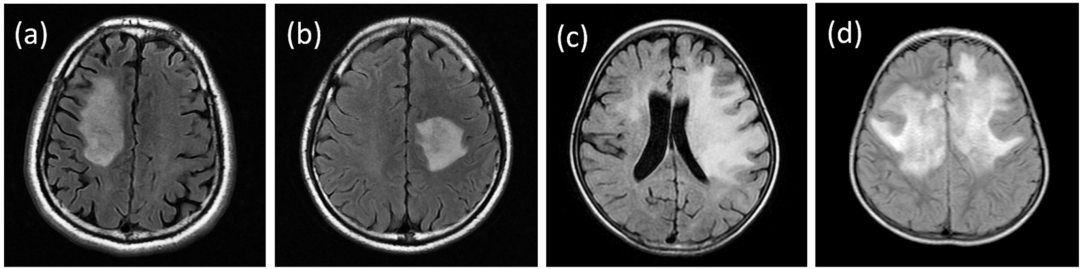

(a、b)脑MRI示直径>2 cm的大病灶;(c、d)脑MRI中的“脑白质营养不良样”病变。